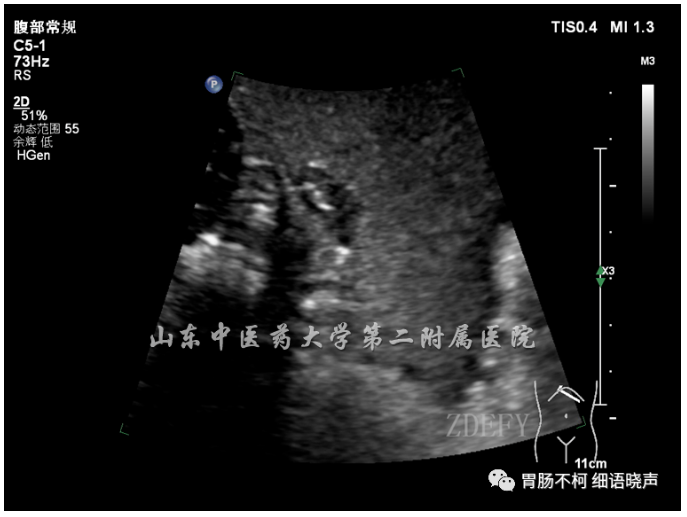

病例三:黏膜下层来源病灶,球状,内呈网格状回声,可见“脐样征”。